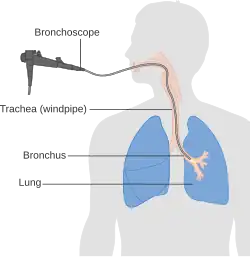

A definitive diagnosis of lung cancer requires a biopsy of the suspected tissue be histologically examined for cancer cells.[12] Given the location of lung cancer tumors, biopsies can often be obtained by minimally invasive techniques: a fiberoptic bronchoscope that can retrieve tissue (sometimes guided by endobronchial ultrasound), fine needle aspiration, or other imaging-guided biopsy through the skin.[12] Those who cannot undergo a typical biopsy procedure may instead have a liquid biopsy taken (that is, a sample of some body fluid) which may contain circulating tumor DNA that can be detected.[13]